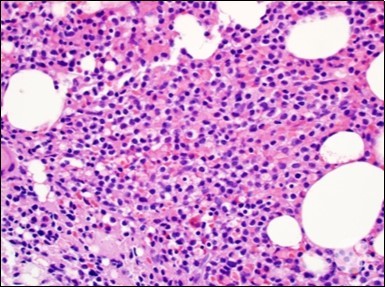

Figure 3.HCL: hairy cells dispersed within the native architecture(19).

The leukaemia cells may enunciate a characteristic immune phenotype, crucial for a confirmatory diagnosis. The peripheral blood mononuclear B cell population may display a kappa or lambda light chain restriction. The phenotype of classic hairy cell leukaemia may be delineated by concurrent, immune reactive CD19+ CD20+,CD 11c+, CD25+, CD103+ and CD123+. An intensely immune reactive CD200+ and a non reactive CD27- antigen may be present2, 4. Evaluation of a trephine bone marrow biopsy and bone marrow aspirate may define the degree of tumour infiltration. A dry tap on account of prominent bone marrow fibrosis may be elucidated at preliminary diagnosis. A decline in the normal haematopoiesis may account for a hypo-cellular marrow in 10% instances. Gradation of cellular infiltrating of the leukaemia within the bone marrow may be appropriately investigated with immune –histochemical stains2, 4. Immune staining for CD20+, annexin 1 and VE1 (a BRAF V600E stain] may validate the diagnosis and precisely analyse the extent of malignant bone marrow infiltration[8]. Determination of BRAF V600E mutation may be critical in therapeutically non responsive individuals with applicable standard therapy or in instances of multitudinous reoccurrences[9]. Deploying inhibitors of BRAF V600E gene may be efficacious in patients impervious to approved therapy. The mutation necessitates a comprehensive scrutiny of the implicated individuals with a sensitive molecular assay which may discern up to < 10% of the hairy leukaemia cells appearing in the peripheral blood smears or bone marrow aspirates diluted with peripheral blood or aspirates elucidating a dry tap[2,4]. Allele specific polymerase chain reaction (PCR) or a next generation sequencing may be optimally employed to circumvent false negative outcomes. If the leukaemia cells are sparse or if particularly sensitive & efficacious molecular techniques are not accessible, the application of appropriate immune histochemical stains to the bone marrow biopsy such as a BRAF V600E mutation stain (VE1) may detect the hairy cells and conclusively diagnose the condition[2,4,10]. Figure 1, Figure 2, Figure 3, Figure 4, Figure 5, Figure 6, Figure 7, Figure 8, Figure 9, Figure 10, Figure 11, Figure 12, Figure 13, Figure 14.

The classic hairy cell is medium sized with a magnitude of 10-14µm. The moderately abundant or variable cytoplasm may be transparent or mildly basophilic. The cellular surface with the characteristic serrated perimeter depicts innumerable fragile or stout extensions of cytoplasm ,particularly discernible on the phase contrast and electron microscopy. The cytoplasm may exhibit vacuoles with occasional azurophilic granules4. The nucleus may be elliptical or reniform, folded or indented with a coarse, reticulated or a finely dispersed chromatin and inconspicuous nucleoli along with infrequent mitosis. Bone marrow aspiration or bone marrow trephine biopsy may be inadequate for diagnosis in 30%-50% individuals4. The trephine sections of the bone marrow may depict a characteristic interstitial pattern of leukaemic infiltration. Generally the bone marrow is hyper-cellular, though it may be hypo-cellular in 10-15% individuals4. The leukaemia cell ingress may be diffuse or partial, although diffuse infiltration is frequent. The partial variety of leukaemic dissemination may be ineptly categorized with an indeterminate differentiation from the uninvolved marrow. The malignant insertions may initially emerge as miniature, undefined, cellular loci. The formalin fixed, paraffin embedded sections may elucidate a crystalline zone or a “halo” appearance of the cells with a circumscribed nucleus on account of the plentiful cytoplasm4. The cellular margins may be intertwined. Fixation of bone marrow smears with Zenker’s fixative may demonstrate a retracted cytoplasm of the hairy cells with a consequent disconnected structure. The bone marrow in the absence of a malignant process may be hypo-cellular or hyper-cellular. Reticulin stains may delineate an enhanced accrual of broad, dense reticulum fibres surrounding the aggregates of leukaemia cells with the fibrous circumlocution of individual malignant cell and fibrotic extensions into the abutting, uninvolved bone marrow4.